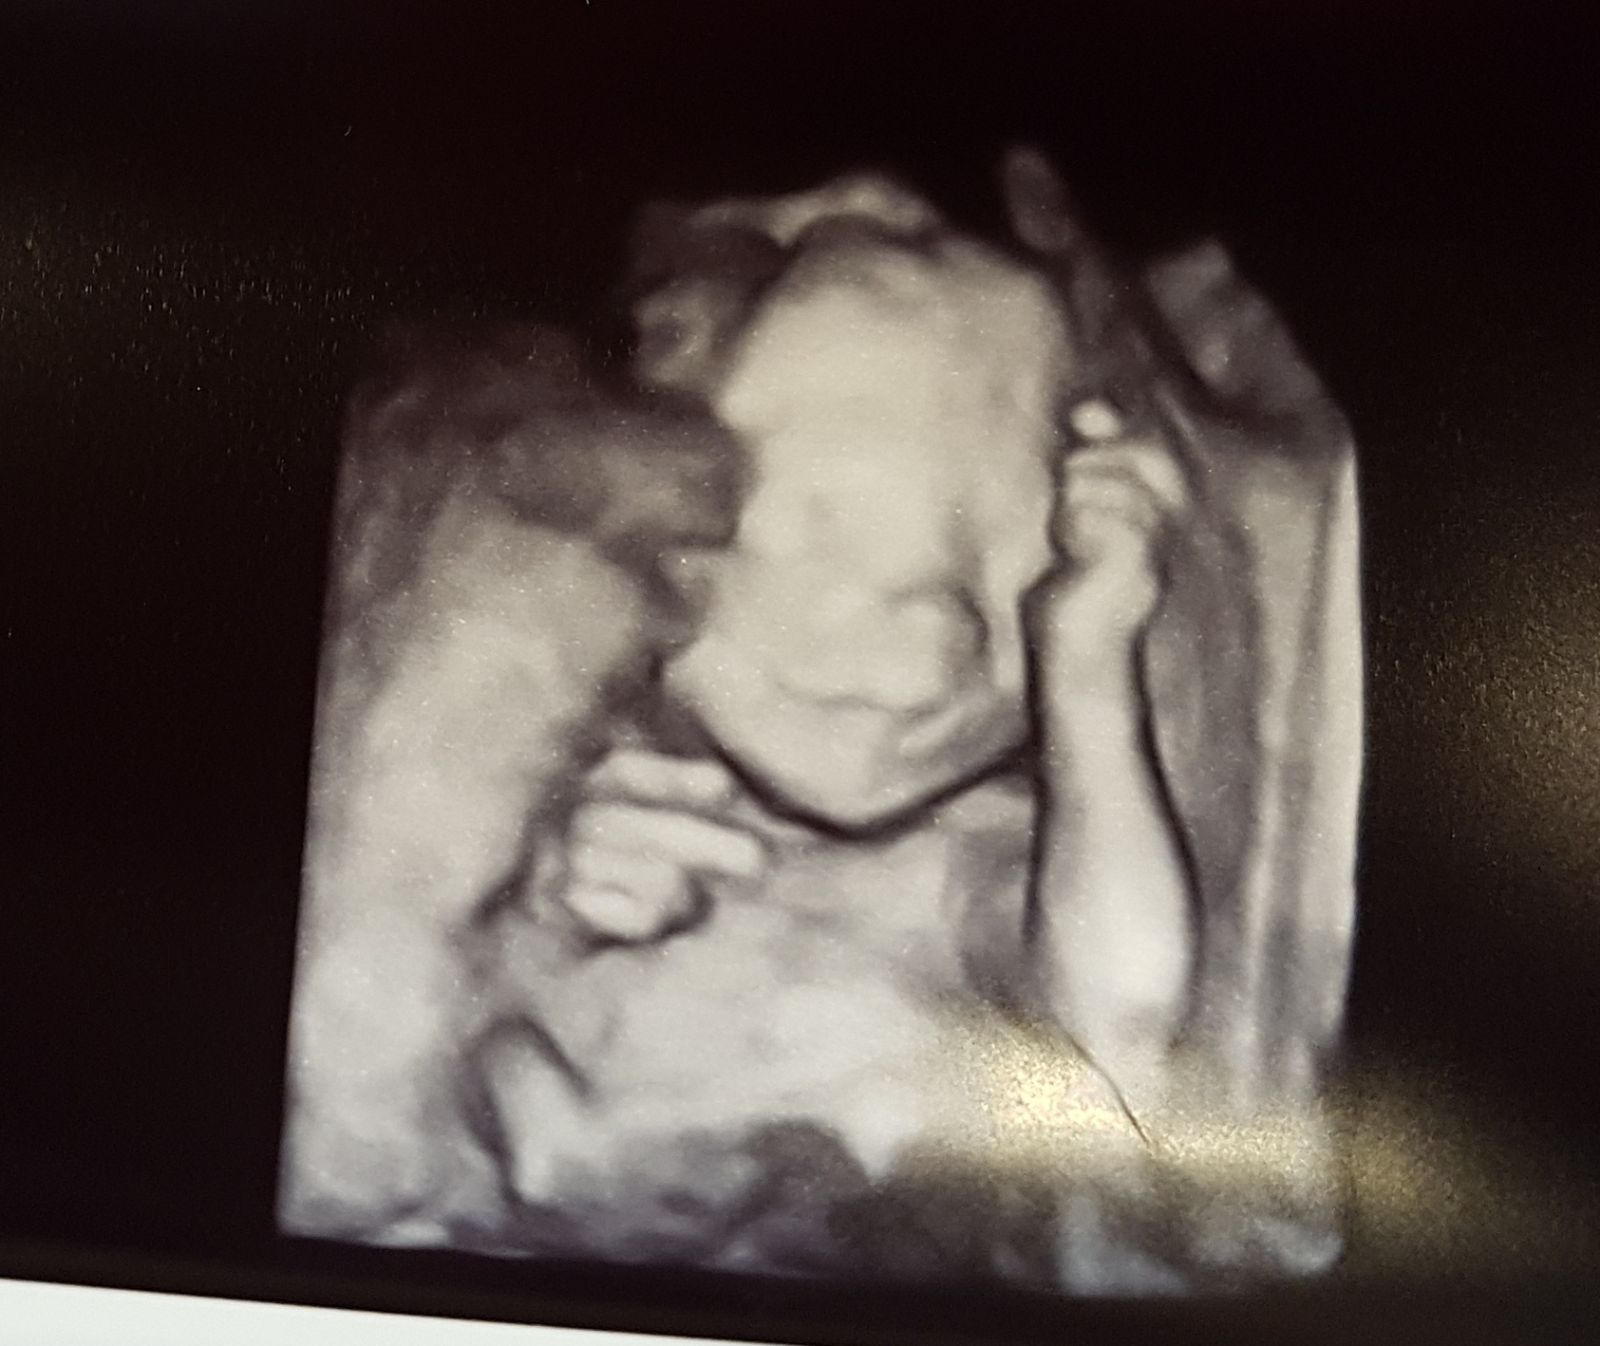

Jestem po wizycie. Z Małą anatomicznie wszystko ok, waży 369g. Moje przepływy się coś lekarzowi nie podobały i muszę mieć kontrolę za dwa tygodnie. Chodzi o wagę dziecka , teraz jest prawidłowa, ale trzeba skontrolować czy będzie prawidłowo przyrastać. Jakaś plamę na sercu widzi ale mówił ze to nie jest żadna wada. Szyjka ok 3,5cm. Tętno 150. Trochę mnie zmartwily te przepływy, chodzi chyba o hipotrofię płodu z tego co czytałam w necie. Nawet nie wiem co mogę zrobić żeby bylo lepiej...teraz niby waga ok ale będę myśleć dwa tygodnie...miała któraś z Was z tym styczność?